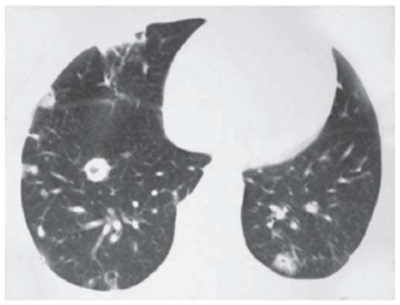

Um paciente de 58 anos de idade, com antecedente pessoal de hipertensão arterial sistêmica, diabetes melito e doença renal crônica estádio 4, pouco aderente ao tratamento medicamentoso, necessitou de internação recente devido a estado hiperglicêmico e hiperosmolar há três semanas. Nesta internação, permaneceu sob cuidados intensivos e, entre outras terapias, foi submetido a quatro sessões de hemodiálise. Desde a alta, melhorou sua adesão medicamentosa, no entanto, vem apresentando calafrios, sudorese e alguns episódios de febre, que o paciente tem atribuído aos medicamentos que agora passou a usar. Há um dia, iniciou quadro de tosse e dor ventilatório-dependente e, devido a isso, resolveu procurar o pronto-socorro. Na triagem, apresentava FC de 101, PA de 160 x 100, T 37,6 e sat. de O2 de 92%. O médico plantonista, sem examinar o doente, solicitou uma tomografia de tórax, que revelou a imagem seguinte.